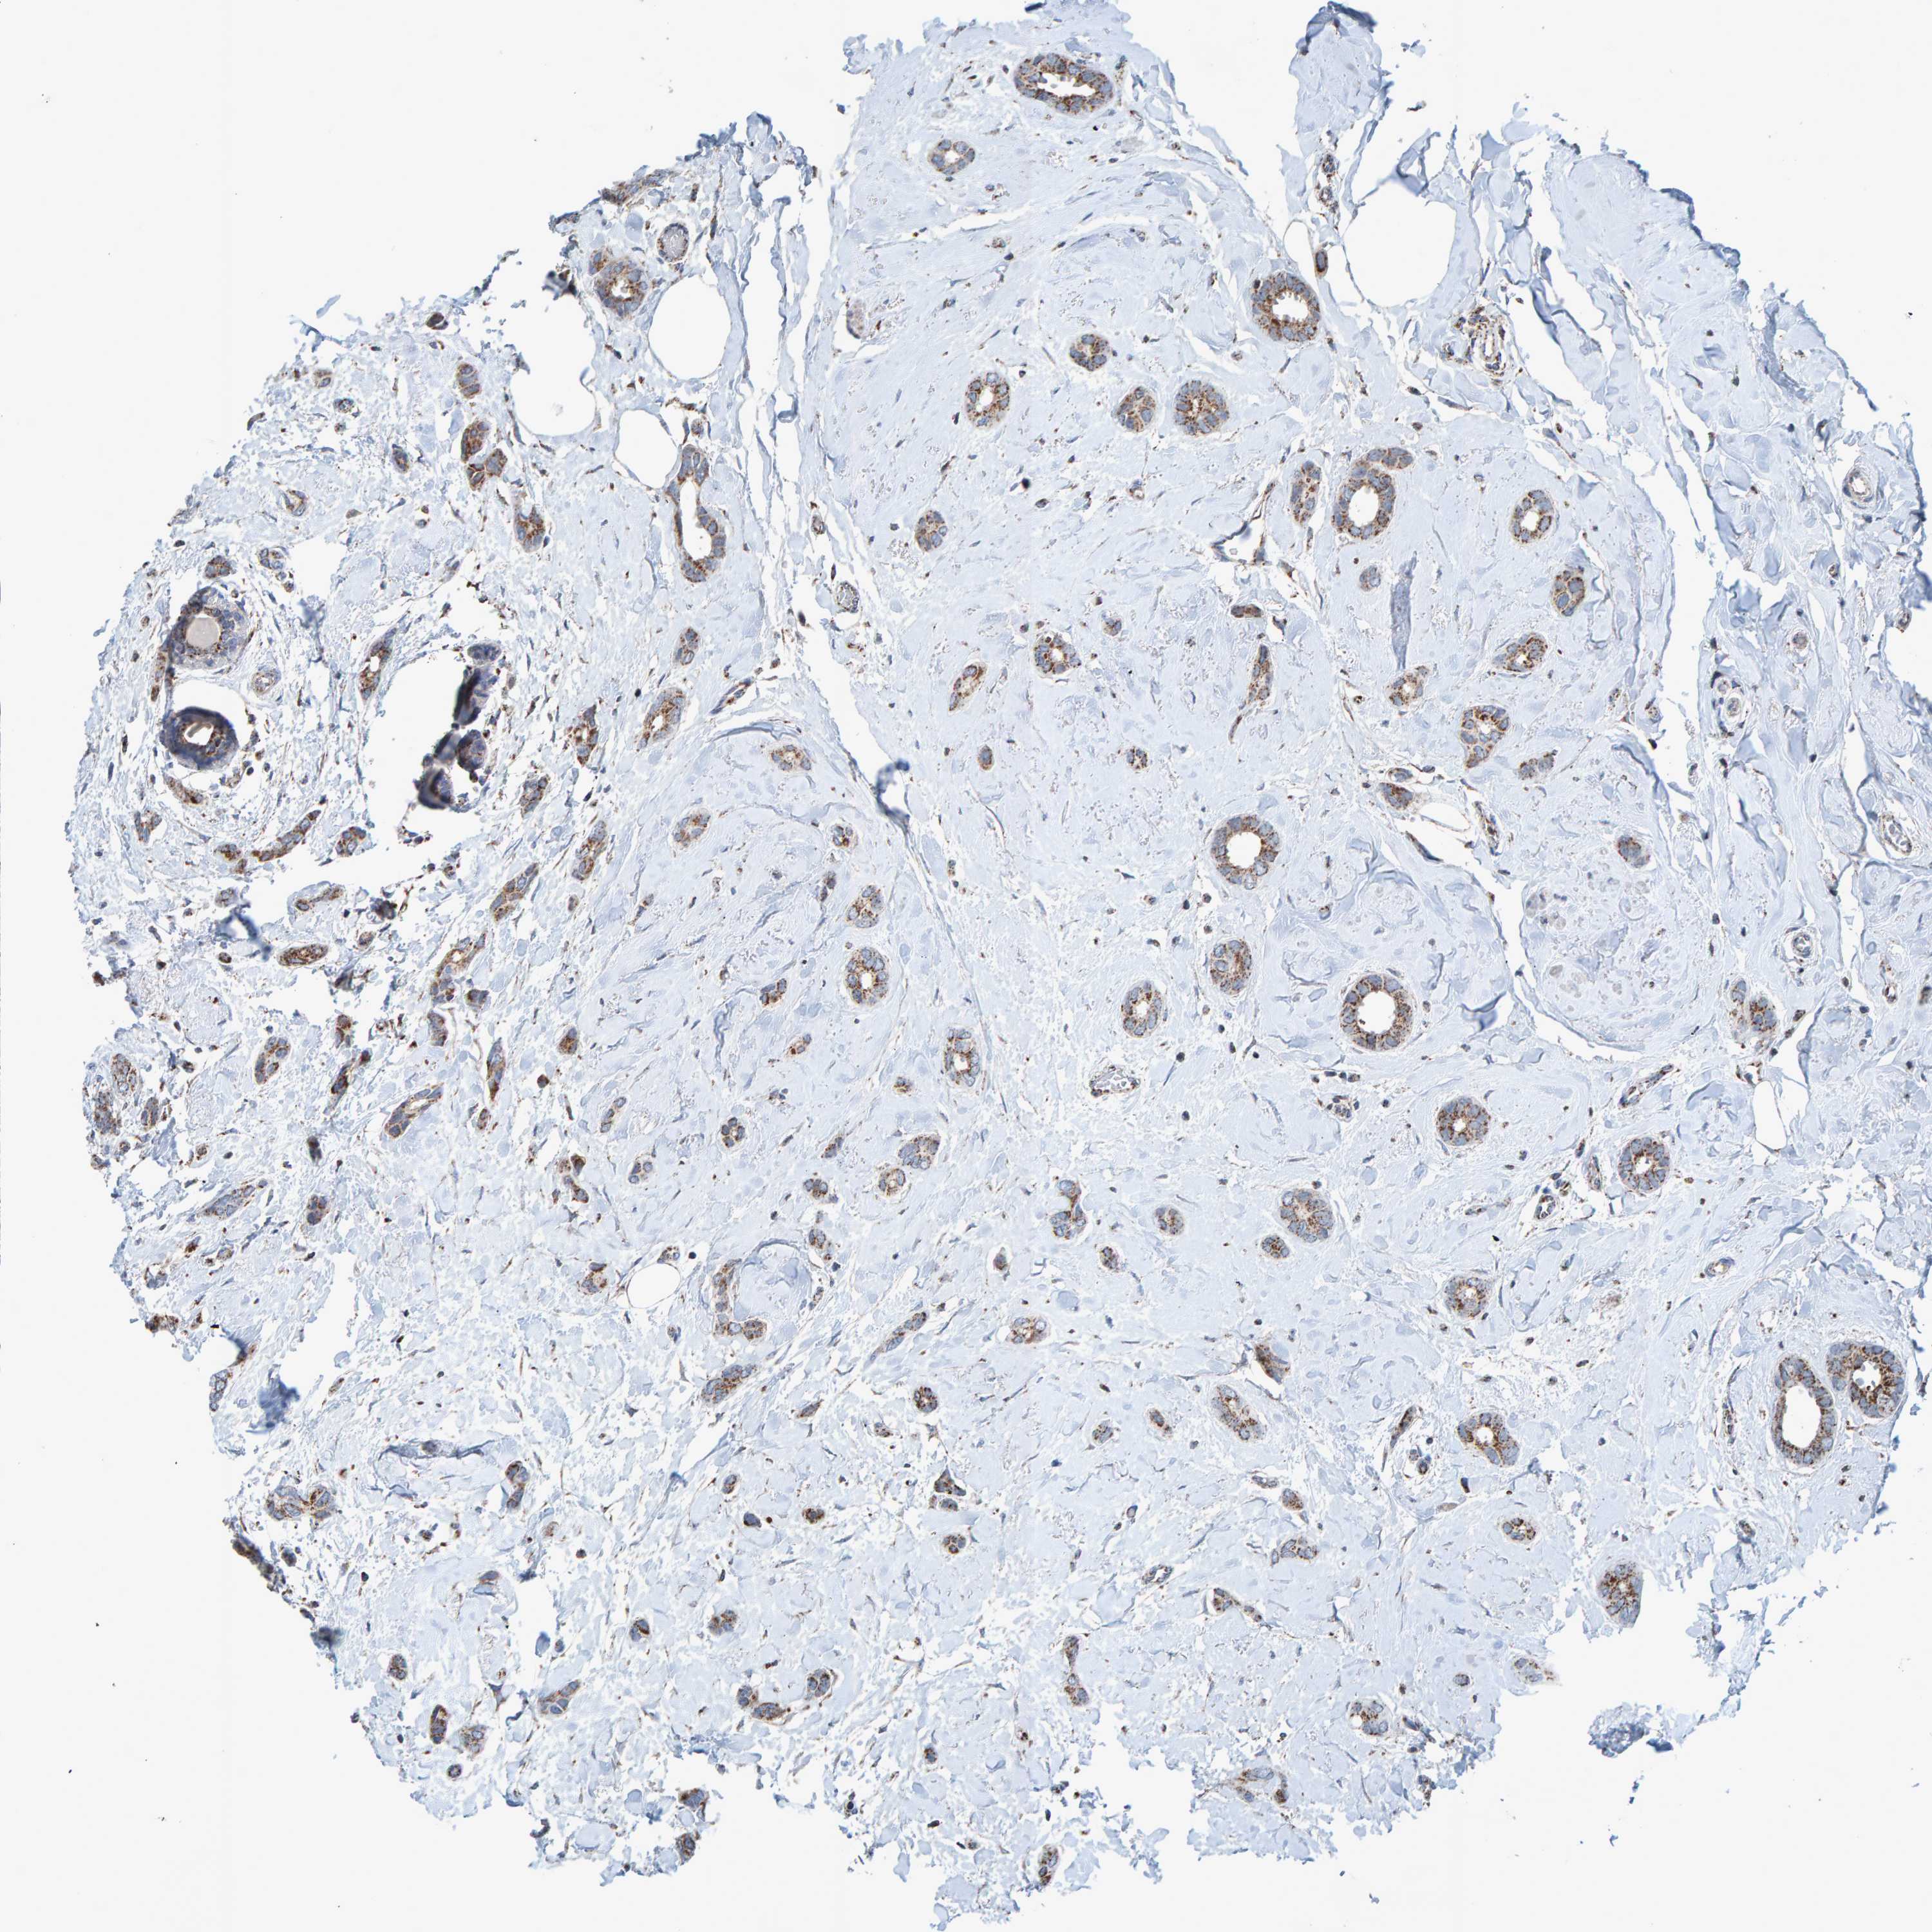

CANCER BREAST CANCER Show tissue menu

BRCA TCGA BRCA VALIDATION PROTEIN EXPRESSION